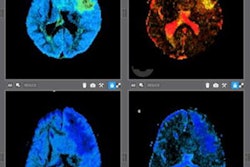

Random Walk's software uses an algorithm that converts standard fractional anisotropy (FA) into a microscopic fractional anisotropy (mFA) on diffusion-tensor MRI. The algorithm is designed to reduce the impact of white-matter fiber orientation on MRI sensitivity, the company noted.

Random Walk's microscopic mapping algorithm improved the detail of MRI scans and helped clinicians to significantly improve the detection of disease-related cerebral white matter degeneration in patients with MS, the researchers found.